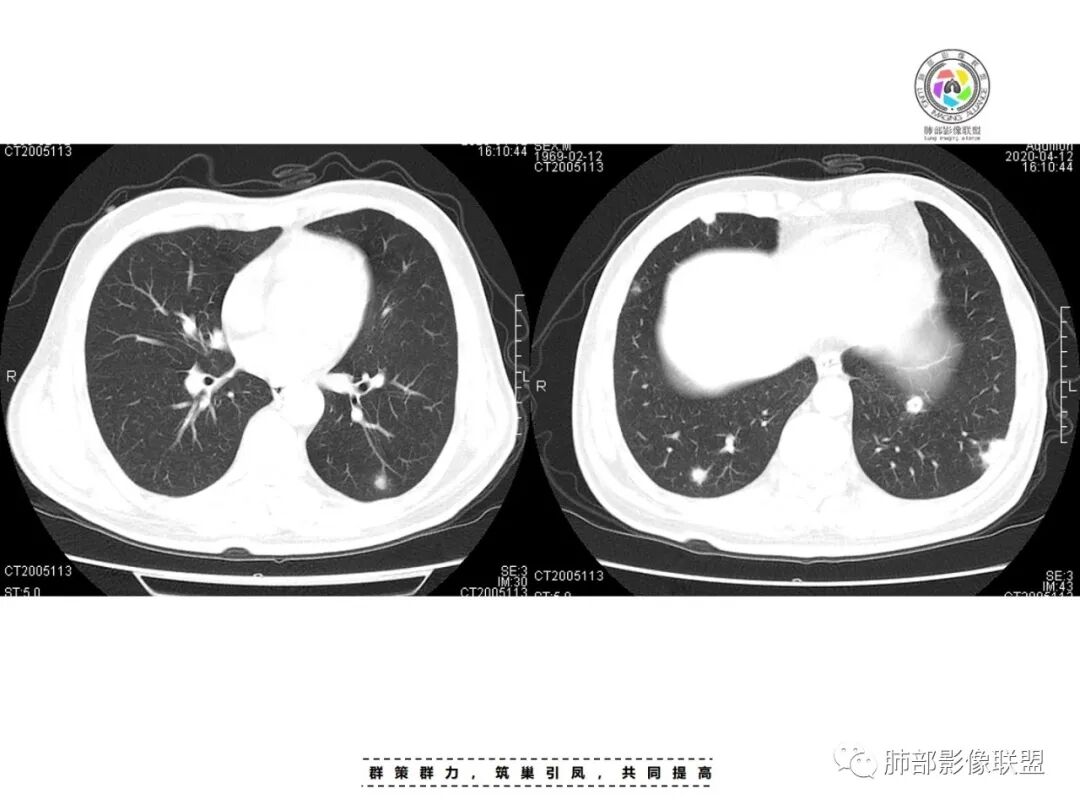

俞丽:患者男性,糖尿病,两肺多发结节,部分伴空洞形成,经治疗后好转,首先考虑感染性病变,肺克可能性大穿越七海的风:糖尿病史,双肺多发结节、空洞,进展快,治疗后吸收,考虑SPE,肺克或金葡飞鹰行动:患者男性,糖尿病病史,CT可见双肺多发结节,多位于胸膜下,部分伴空洞形成,经治疗后好转,首先考虑感染性病变,金黄色葡萄球菌或肺克需要考虑,患者病灶分散,双肺病灶血道来源,肝脏未见病灶,金黄色葡萄球菌感染可能性大一些。

李:双肺多发结节,部分空洞,胸膜下为主,考虑血源性,治疗后好转,如果抗炎好转,考虑化脓菌栓,肺克或金葡,如激素治疗后考虑gpa亚东:双肺多发结节,部分见空洞,与血管关系紧密,考虑感染性病变,短期内变化快,糖尿病史,金葡,肺克?王秀仙:糖尿病基础上伴发的多发结节,部分空洞,四大金刚金毛结克,首选肺克琦遇:糖尿病四大金刚里按病史只有金葡和肺克符合,病灶特点,胸膜下为主,病灶偏少,有不干净空洞,肝功无异常,金葡可能性大!大雄:但是没有发热 小强:糖尿病史,胸膜下,6天空洞增大,金葡可能,肺克一般进展后有融合大片改变,这个没有,但是金葡临床症状更重,这个也看不出来崔少钢:中年男性,血糖控制不良,感染指标高。影像:双肺多发的结节、空洞,分布比较随机,考虑肺克。病变变化不够快,囊张力不够高,感觉不像金葡。大雄:血流感染的金葡 与肺克影像上有重叠,不一定好区分肺克炎性指标(PCT)可以高的更明显金葡血流感染一般有可追寻的来源,比如皮损,软组织脓肿,骨髓炎,心内膜炎等肺克一般是来源肠道,经门脉系统入肝,形成肉眼可见的肝脓肿或者不可见的隐匿性微脓肿,再经肝静脉回流→下腔静脉→右心→肺动脉→肺内播散张小兵:糖尿病基础,胸膜下多发结节伴空洞形成,这么大的空洞结节无播散,排除结核。肉芽肿性多血管炎,一般累及支气管,引起支气管狭窄,也可排除,倾向肺克,鉴别金葡。流心明智:男性,51岁,以咳嗽、咳痰、气喘3天。既往糖尿病10年。血常规wBC及中性比、CRP、PCT均升高。CT示:双肺多发结节、小斑片影,胸膜下多,大部分实性、部分伴空洞,大部分类圆形、部分呈楔形,部分病灶可见滋养血管征,治疗后逐渐吸收。考虑:感染性病变,SPE,金葡>肺克,鉴别隐球、TB等。

一、双肺多发结节或小片影,随机分布,而未见支气管壁增厚及支气管远端如树芽征等改变,提示病灶来源于血道;且肺内结节边缘模糊,常可排除转移(一般转移瘤边缘多较光整,患者常有恶性肿瘤病史,且呼吸道症状不明显或出现较迟);

影像表现:双侧结节,常伴空洞形成,最多见于肺外周和肺下野,结节的边界清晰或模糊;可伴有斑片状实变区;多表现为基底贴近胸膜的楔形实变影,其内密度均匀或不均匀,可形成空洞。